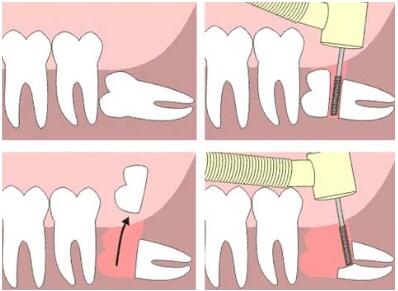

拔牙步骤

大连康贝佳口腔采用微创微痛拔牙技术,让拔牙不再痛。在拔牙过程中,避免了敲击、减少骨壁的损伤机会、消除拔牙断根现象,简化了拔牙过程,缩短了手术时间,减轻了病人的恐惧和痛苦,有效减少了并发症。并大限度保存了牙槽骨,对种植牙、镶牙都提供了有利条件。而且使人们在拔牙过程中轻轻松松,特别受老年人、精神紧张患者和种植牙患者的欢迎。